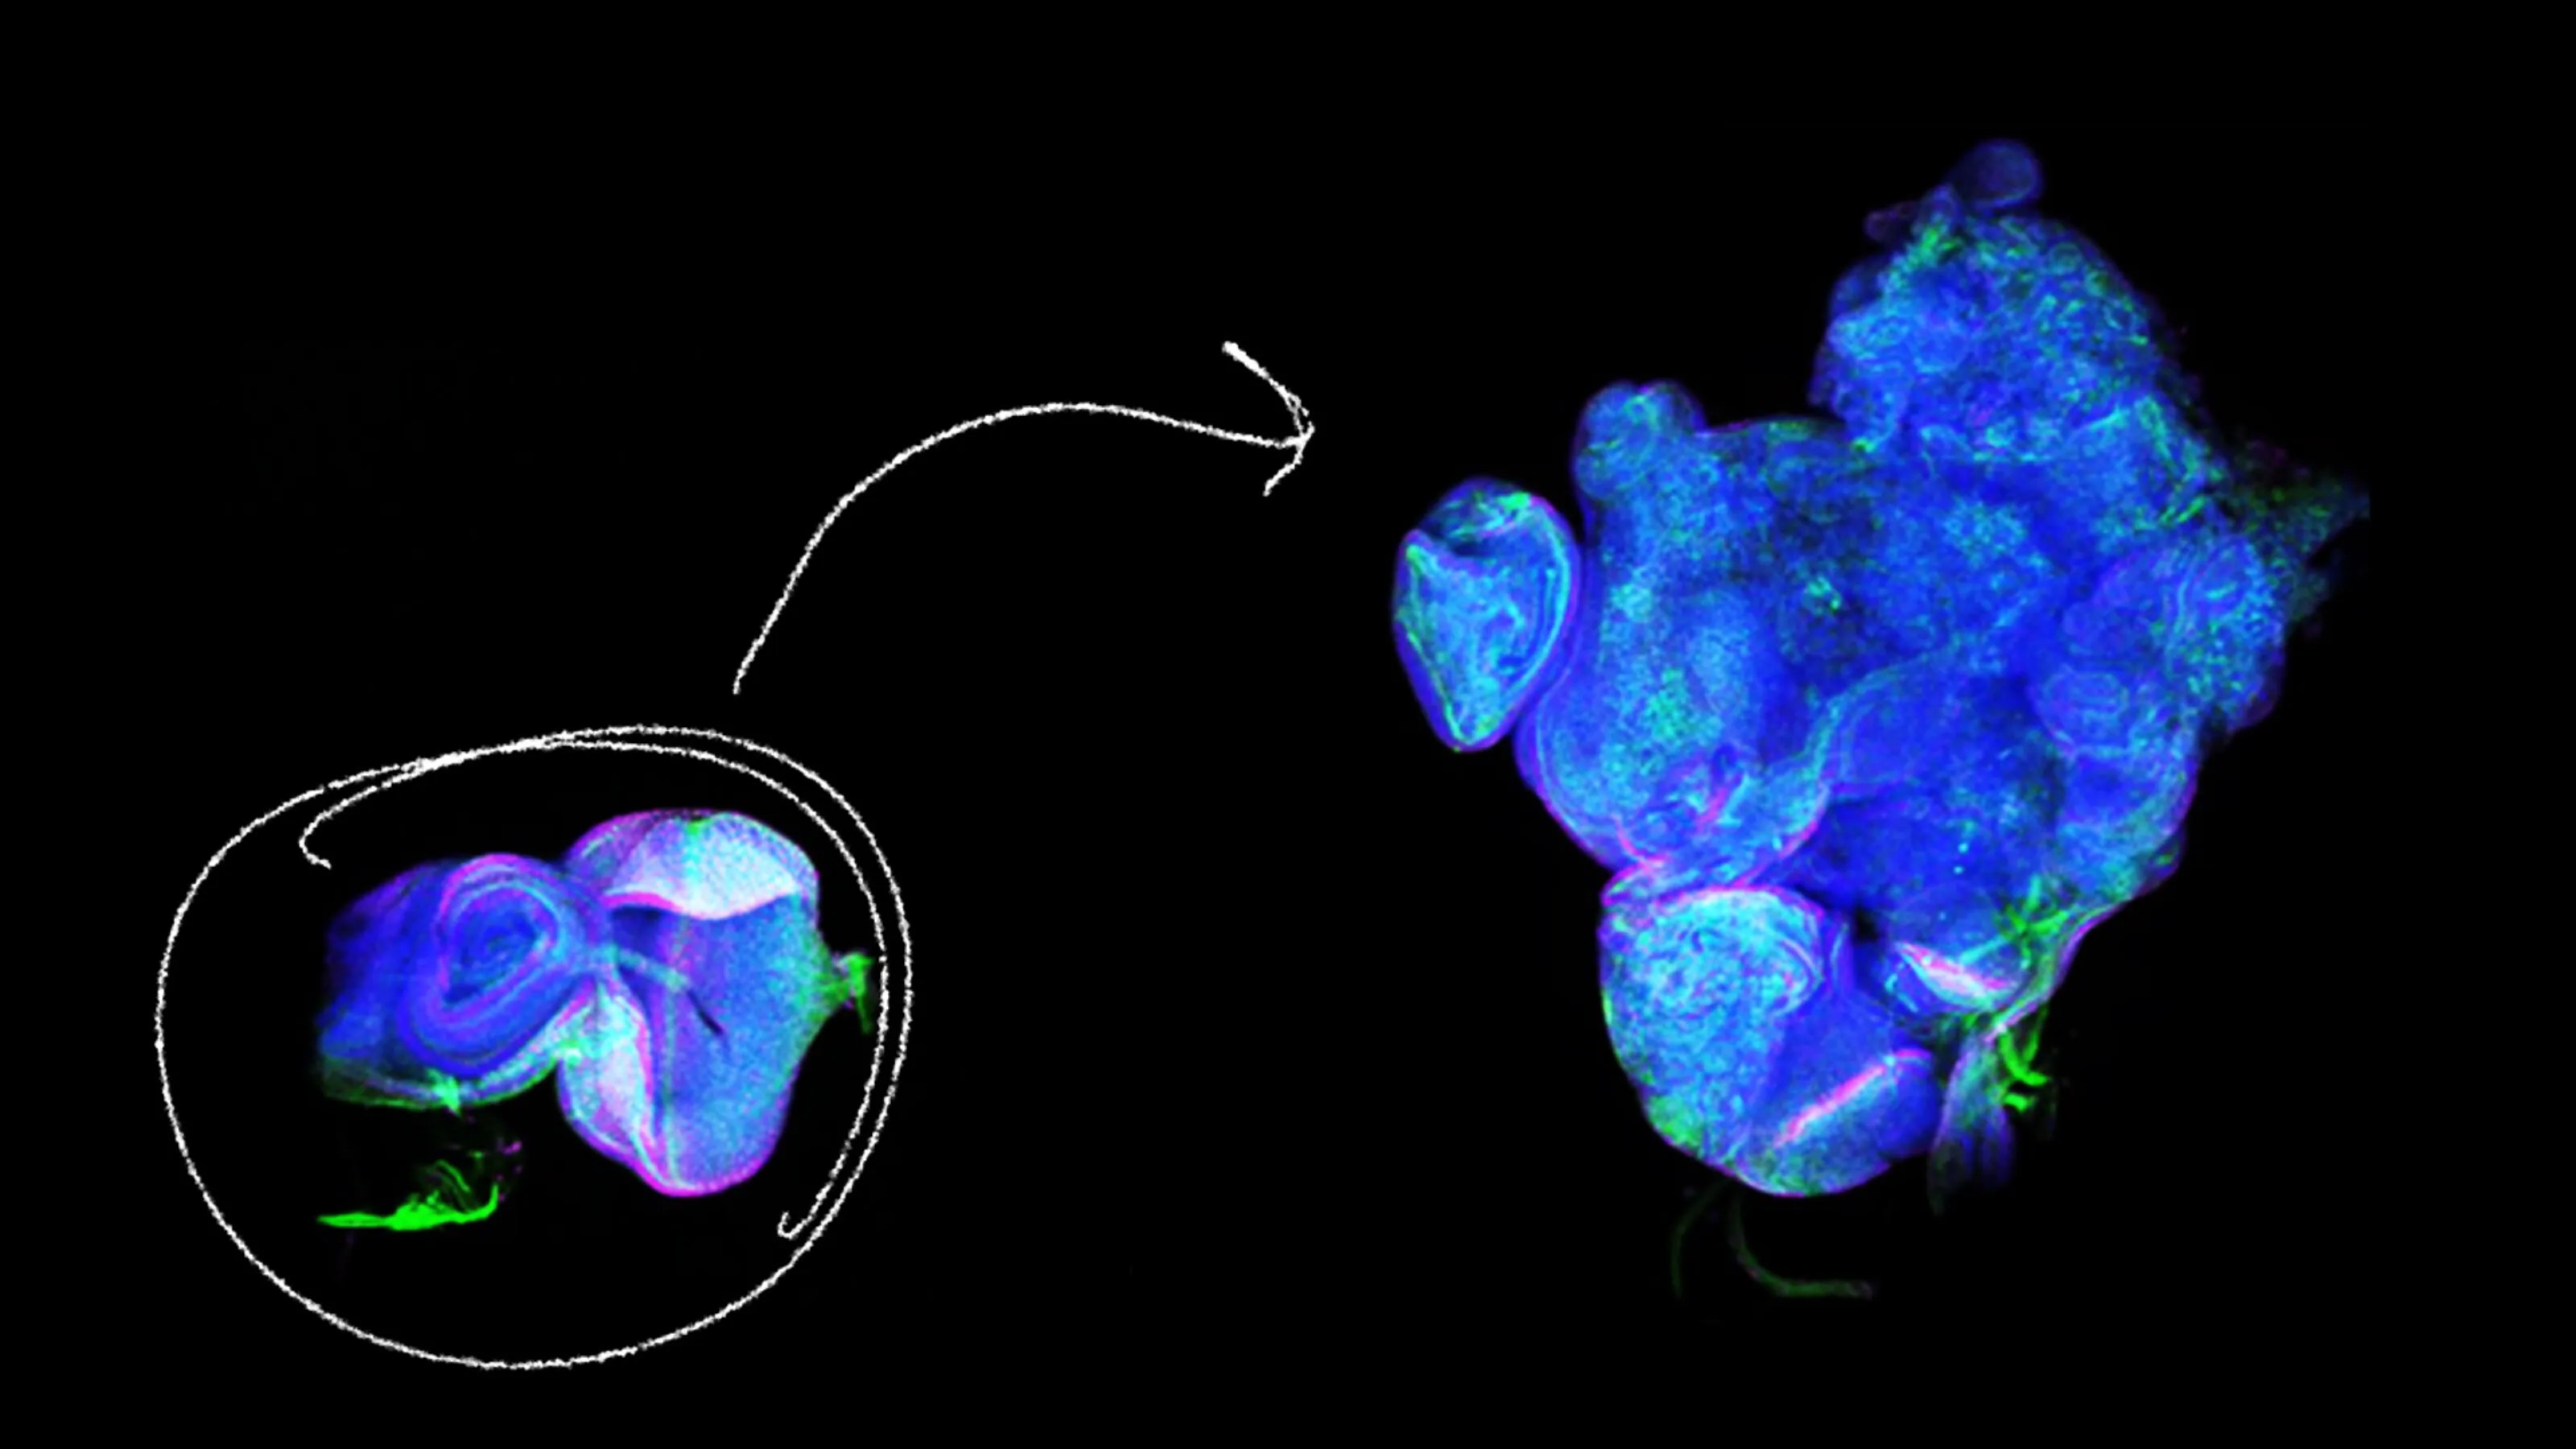

“Having more stem cell activity is good for regeneration, but too much of a good thing over time can have less favorable consequences.”

They call it “Judo T-cell therapy,” and it’s 100 times more potent than regular CAR-T cells.